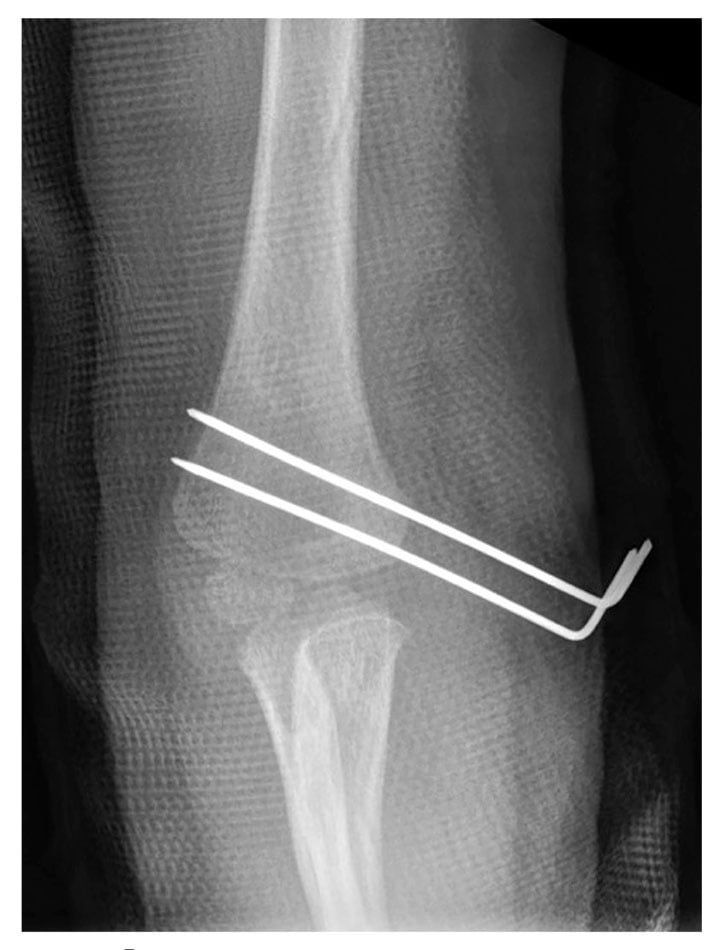

MR images revealed an avulsion fracture of the right medial condyle and epicondyle. The fragment was displaced medially and rotated; the articular surface was oriented laterally facing the distal humerus, which correlated with the calcification seen on previous radiographs. The displaced, predominately cartilaginous, trochlear and medial epicondyle fracture fragment was visible on cartilage-specific fat-suppressed T1 volume sequences (see Figure 3). MR images were sent to the 3-D Innovation Laboratory and processed into 3-D volume-rendered images for surgical planning using a sequence that isolates bone and cartilage from adjacent structures. Orthopedic surgeons evaluated the images, and determined that an open reduction and internal fixation surgical procedure was required. They performed the procedure on the trochlea and medial epicondyle, using Kirschner wires to repair the fracture. A postoperative radiograph, obtained while the elbow was in a cast, showed Kirschner wire placement and confirmed fracture repair (see Figure 4).

Figure 4. Postoperative repair of the medial condyle and epicondyle avulsion fracture with Kirschner wires in place. Image courtesy of the authors.